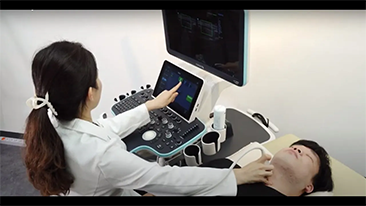

????? ??? ??? ??? ?? ?? ???? ????, ?????? ??? ?? ???? ?? ??? ??? ??? ??? ?? ???? ?? ???? ????? ???.

??? ?? ??? ?? ???? ? ??? ?? ??? ?? ??? ??? ??? ???. ???? ??? UWN+ ?? ?? ??? ?? MI??? ??? ??? ?? ?? ??? ?? ?? ?? ???, ?? ?? ?? ???? ??? ? ????.